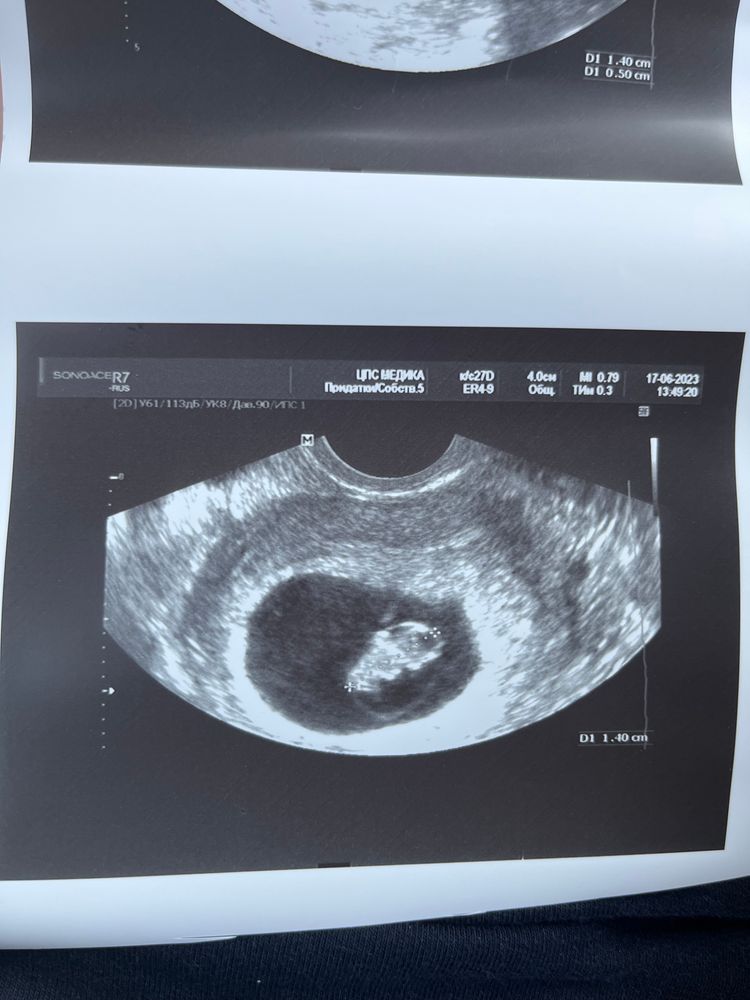

Плановые сроки узи

Плановые сроки узи 114 фотографий